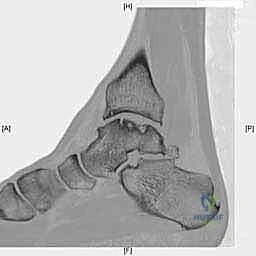

- التصوير المقطعي المحوسب (CT Scan): ضروري جداً للآفات الكبيرة. يوفر الـ CT صورة ثلاثية الأبعاد للعظم، مما يساعد الجراح في التخطيط الدقيق لعملية قطع العظم وحجم الطعم المطلوب زراعته.

لفهم طبيعة العلاج، يجب أولاً أن نفهم طبيعة المرض بشكل عميق. آفة العظم الغضروفي في الكاحل هي منطقة محددة من التلف والتمزق تصيب الغضروف المفصلي والعظم الأساسي (Subchondral bone) الذي يقع تحته مباشرة في الجزء العلوي من عظم الكاحل (قبة التالوس)، والذي يشكل الجزء السفلي والمحوري من مفصل الكاحل.

لفهم أهمية وصعوبة هذه الجراحة، من الضروري والمهم جداً أن نلقي نظرة طبية دقيقة على تشريح الكاحل. الكاحل ليس مجرد مفصل بسيط، بل هو تحفة هندسية حيوية، مفصل معقد يتحمل وزن الجسم كاملاً بالإضافة إلى قوى مضاعفة أثناء الأنشطة الرياضية. يتكون مفصل الكاحل من التقاء ثلاثة عظام رئيسية:

عظم الكاحل (التالوس): حجر الزاوية

عظم الكاحل هو عظم فريد من نوعه في جسم الإنسان. يتميز بأن الغضروف المفصلي يغطي حوالي 60% إلى 70% من مساحة سطحه الكلية. لا توجد أوتار أو عضلات تلتصق به مباشرة، بل يعتمد بالكامل على الأربطة لتثبيته. إنه بمثابة "حجر الزاوية" في قبو مفصل الكاحل، حيث يتمفصل من الأعلى مع عظم الظنبوب لتكوين المفصل الظنبوبي الكاحلي (Tibiotalar joint)، ومن الداخل مع الكعب الإنسي (Medial Malleolus)، ومن الخارج مع الكعب الوحشي (Lateral Malleolus). هذه الترتيبات الهندسية المعقدة هي التي تسمح بحركة الانثناء الأخمصي والانثناء الظهري (رفع وخفض القدم) الضرورية للمشي والجري.